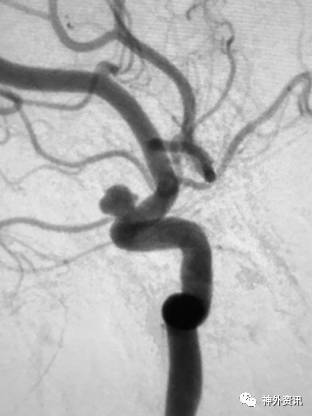

大C塑形

10mm以上的大动脉瘤:

(1)C型头端完全进入动脉瘤囊内,微导管的盘旋有利于均匀填塞

(2)避免微导管头端过早踢出

病例一